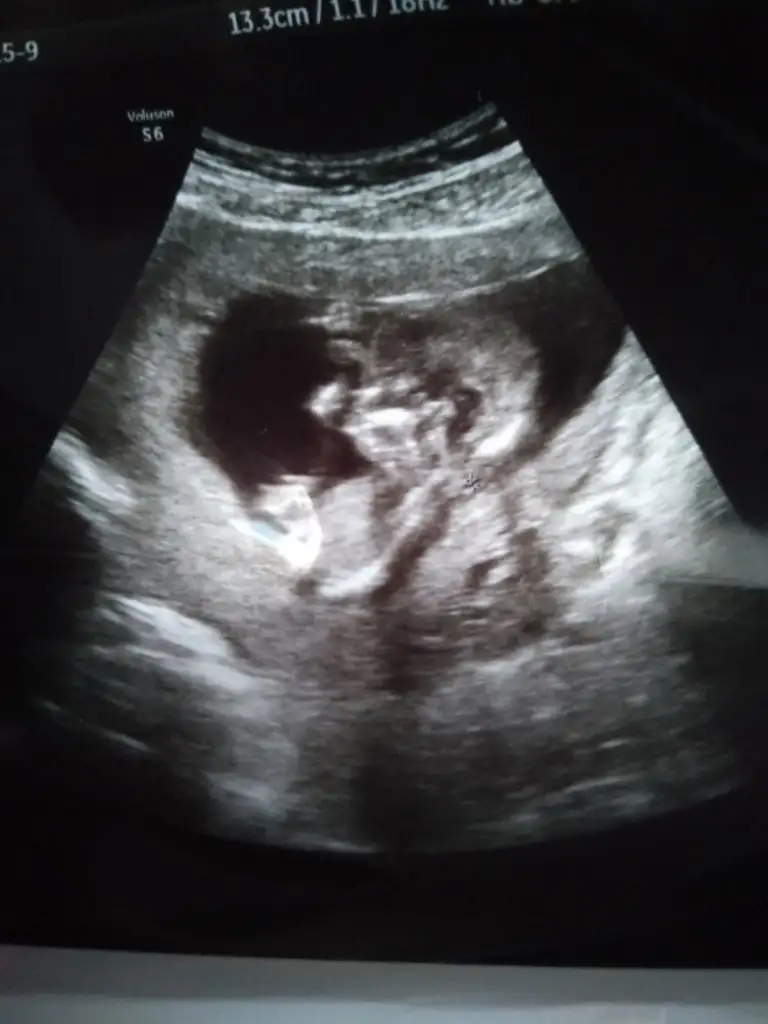

Erkek gibi sankiIkra meyra bir tahminde bulunabilir misiniz acaba. 13 haftalık ama ultrasonda 1 hafta önde gidiyor

Teşekkürler doktorda erkeğe benzetti ama pozisyon itibariyle çok net olamadi birdahaki ay kesin dediErkek gibi sanki

Net görüyormusunKız görünüyor

Diğer usg netti canım bence erkek diğer USG ileNet görüyormusun

Evet dik görünüyor erkekAçı paralel değil yani dimi , burada öle görünüyor